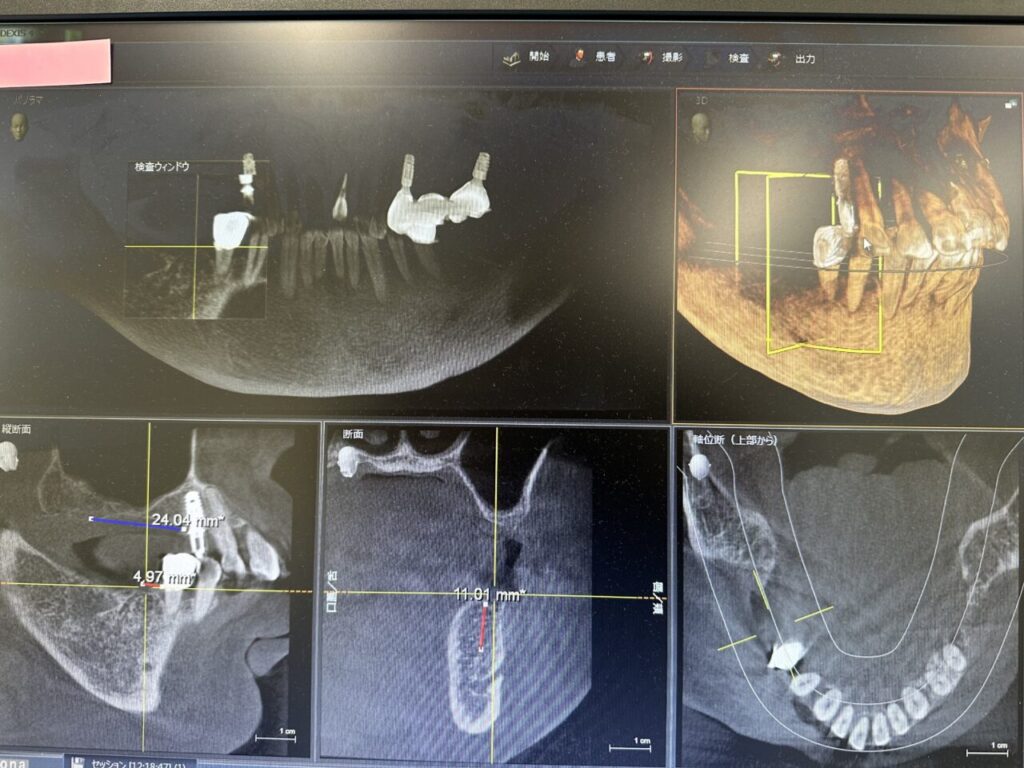

3次元CT撮影と3Dシミュレーション

デンツプライシロナ社製(ドイツ)ORTHOPHOS XGでCT撮影を行っています。

3D画像解析はSIDEXIS 4を用い、3次元的な骨の量や歯の位置関係を1/100mm単位で精密に計測し診査します。

インプラント埋入位置の3DシミュレーションはGALILEOS Implantを用い、1次オペのガイド製作に活用しています。

美味しくご飯が食べられて,審美的で衛生的な長期間安定するインプラントを得るためには,十分な骨の量が必要です.骨の計測は3次元CT撮影で解析した画像を精査して行います.骨がない,足りない場合は骨作りから治療する場合があります.